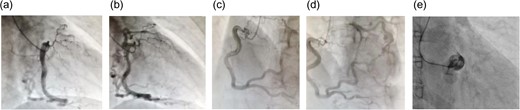

We performed off-pump CABG to treat this patient. We anastomosed the left internal thoracic artery to the left anterior descending coronary artery and the right internal thoracic artery to the left marginal artery. The patient’s hemodynamics were stable during and after the operation. The patient’s postoperative progress was smooth; her ventilator was removed the day after the operation, she began walking independently on Day 3 post-operation, and she was discharged on Day 8 post-operation. Graft patency was confirmed with coronary CT on Day 7 post-operation (Fig. 3). She goes well without any symptoms during 3-years follow up.

Postoperative coronary angiography. Complete graft patency was confirmed.